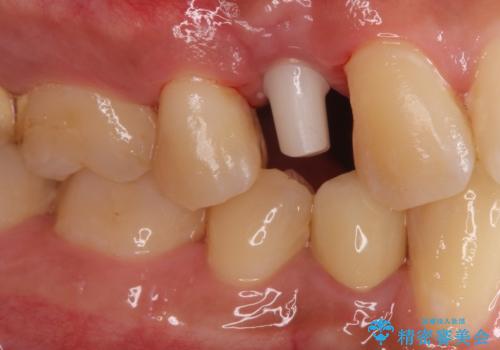

インプラントによる咬合回復を行いました。

インプラントによる治療は隣在歯を削らずに咬合回復できるという利点があります。

セラミッククラウンにより自然な見た目で修復できました。